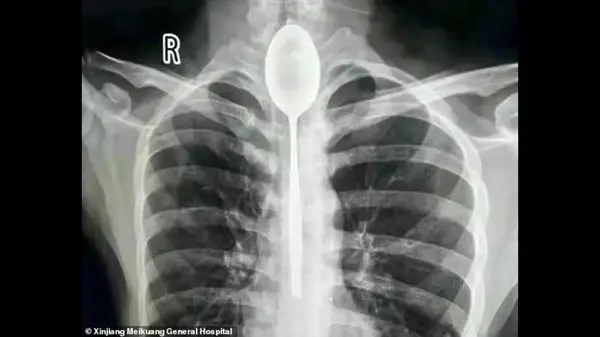

یک سال زندگی این مرد با قاشقی در گلو + عکس

حوادث رکنا: یک مرد چینی قاشقی را قورت داد و قاشق یک سال در گلوی او بود.

به گزارش رکنا،یک مرد چینی یک سال زندگی خود را در حالی سپری کرد که یک قاشق در گلو ی او گیر کرده بود.

مرد چینی در یک شرط بندی احمقانه قاشق 20 سانتی را بلعید و از آنجایی که مشکلی در خوردن و آشامیدن نداشت تا یکسال این قاشق داخل گلوی وی ماند.

مرد چینی قاشق فلزی 8 اینچی را به عنوان یک شیرین کاری احمقانه در سال گذشته بلعید. قاشق در مری او گیر کرد، اما چون به راحتی می توانست بخورد و بنوشد، هرگز به دنبال کمک پزشکی برای بیرون آوردن آن نبود. او می گوید تنها چند روز پیش به علت ضربه وارد شده به قفسه سینه ، دچار درد قفسه سینه شد.

مردی که نامش فاش نشده است از منطقه جین جیانگ چین به پزشکان گفت :او یک قاشق فولادی ضد زنگ را در طی یک شرط درحالت مستی بلعیده . او به دوستانش گفته که می تواند قاشق را ببلعد و بعد دوباره با ریسمانی که به دسته قاشق می بندد آن را بیرون آورد . در آن زمان برای او حتما فکر خوبی به نظر می رسید، اما همه چیز طبق برنامه پیش نرفت و قاشق در گلوی او گیر کرد. به جای رفتن به بیمارستان، مرد منتظر ماند تا ببیند آیا قاشق به طور عادی از خوردن و نوشیدن جلوگیری می کند یا نه ؛ این طور نبود، پس در مری ماند تا سال گذشته.

قاشق مدت طولانی در سینه او مانده بود و براثر ضربه ای که به سینه او وارد شده بود باعث درد شدید و تنفس بدبو او شده بود . سرانجام به بیمارستان عمومی جین جیانگ رفت و به پزشکان گفت یک سال است که قاشق فلزی در مری او گیر کرده است.

دکتر یو در بیانیه ای که توسط بیمارستان منتشر شد ، نوشت:من هرگز چنین چیزی ندیده ام ؛ شوکه شده بودم.

پزشکان در بیمارستان عمومی جین جیانگ پس از بحث در مورد بهترین مسیر عمل تصمیم گرفتند که بهترین راه خارج کردن قاشق ، از طریق دهان بوده است. داروی بی هوشی به بیمار دادند و یک تیم دو ساعت تلاش کردند تا با استفاده از تجهیزات آندوسکوپی ، قاشق 8 اینچی را بیرون آوردند.